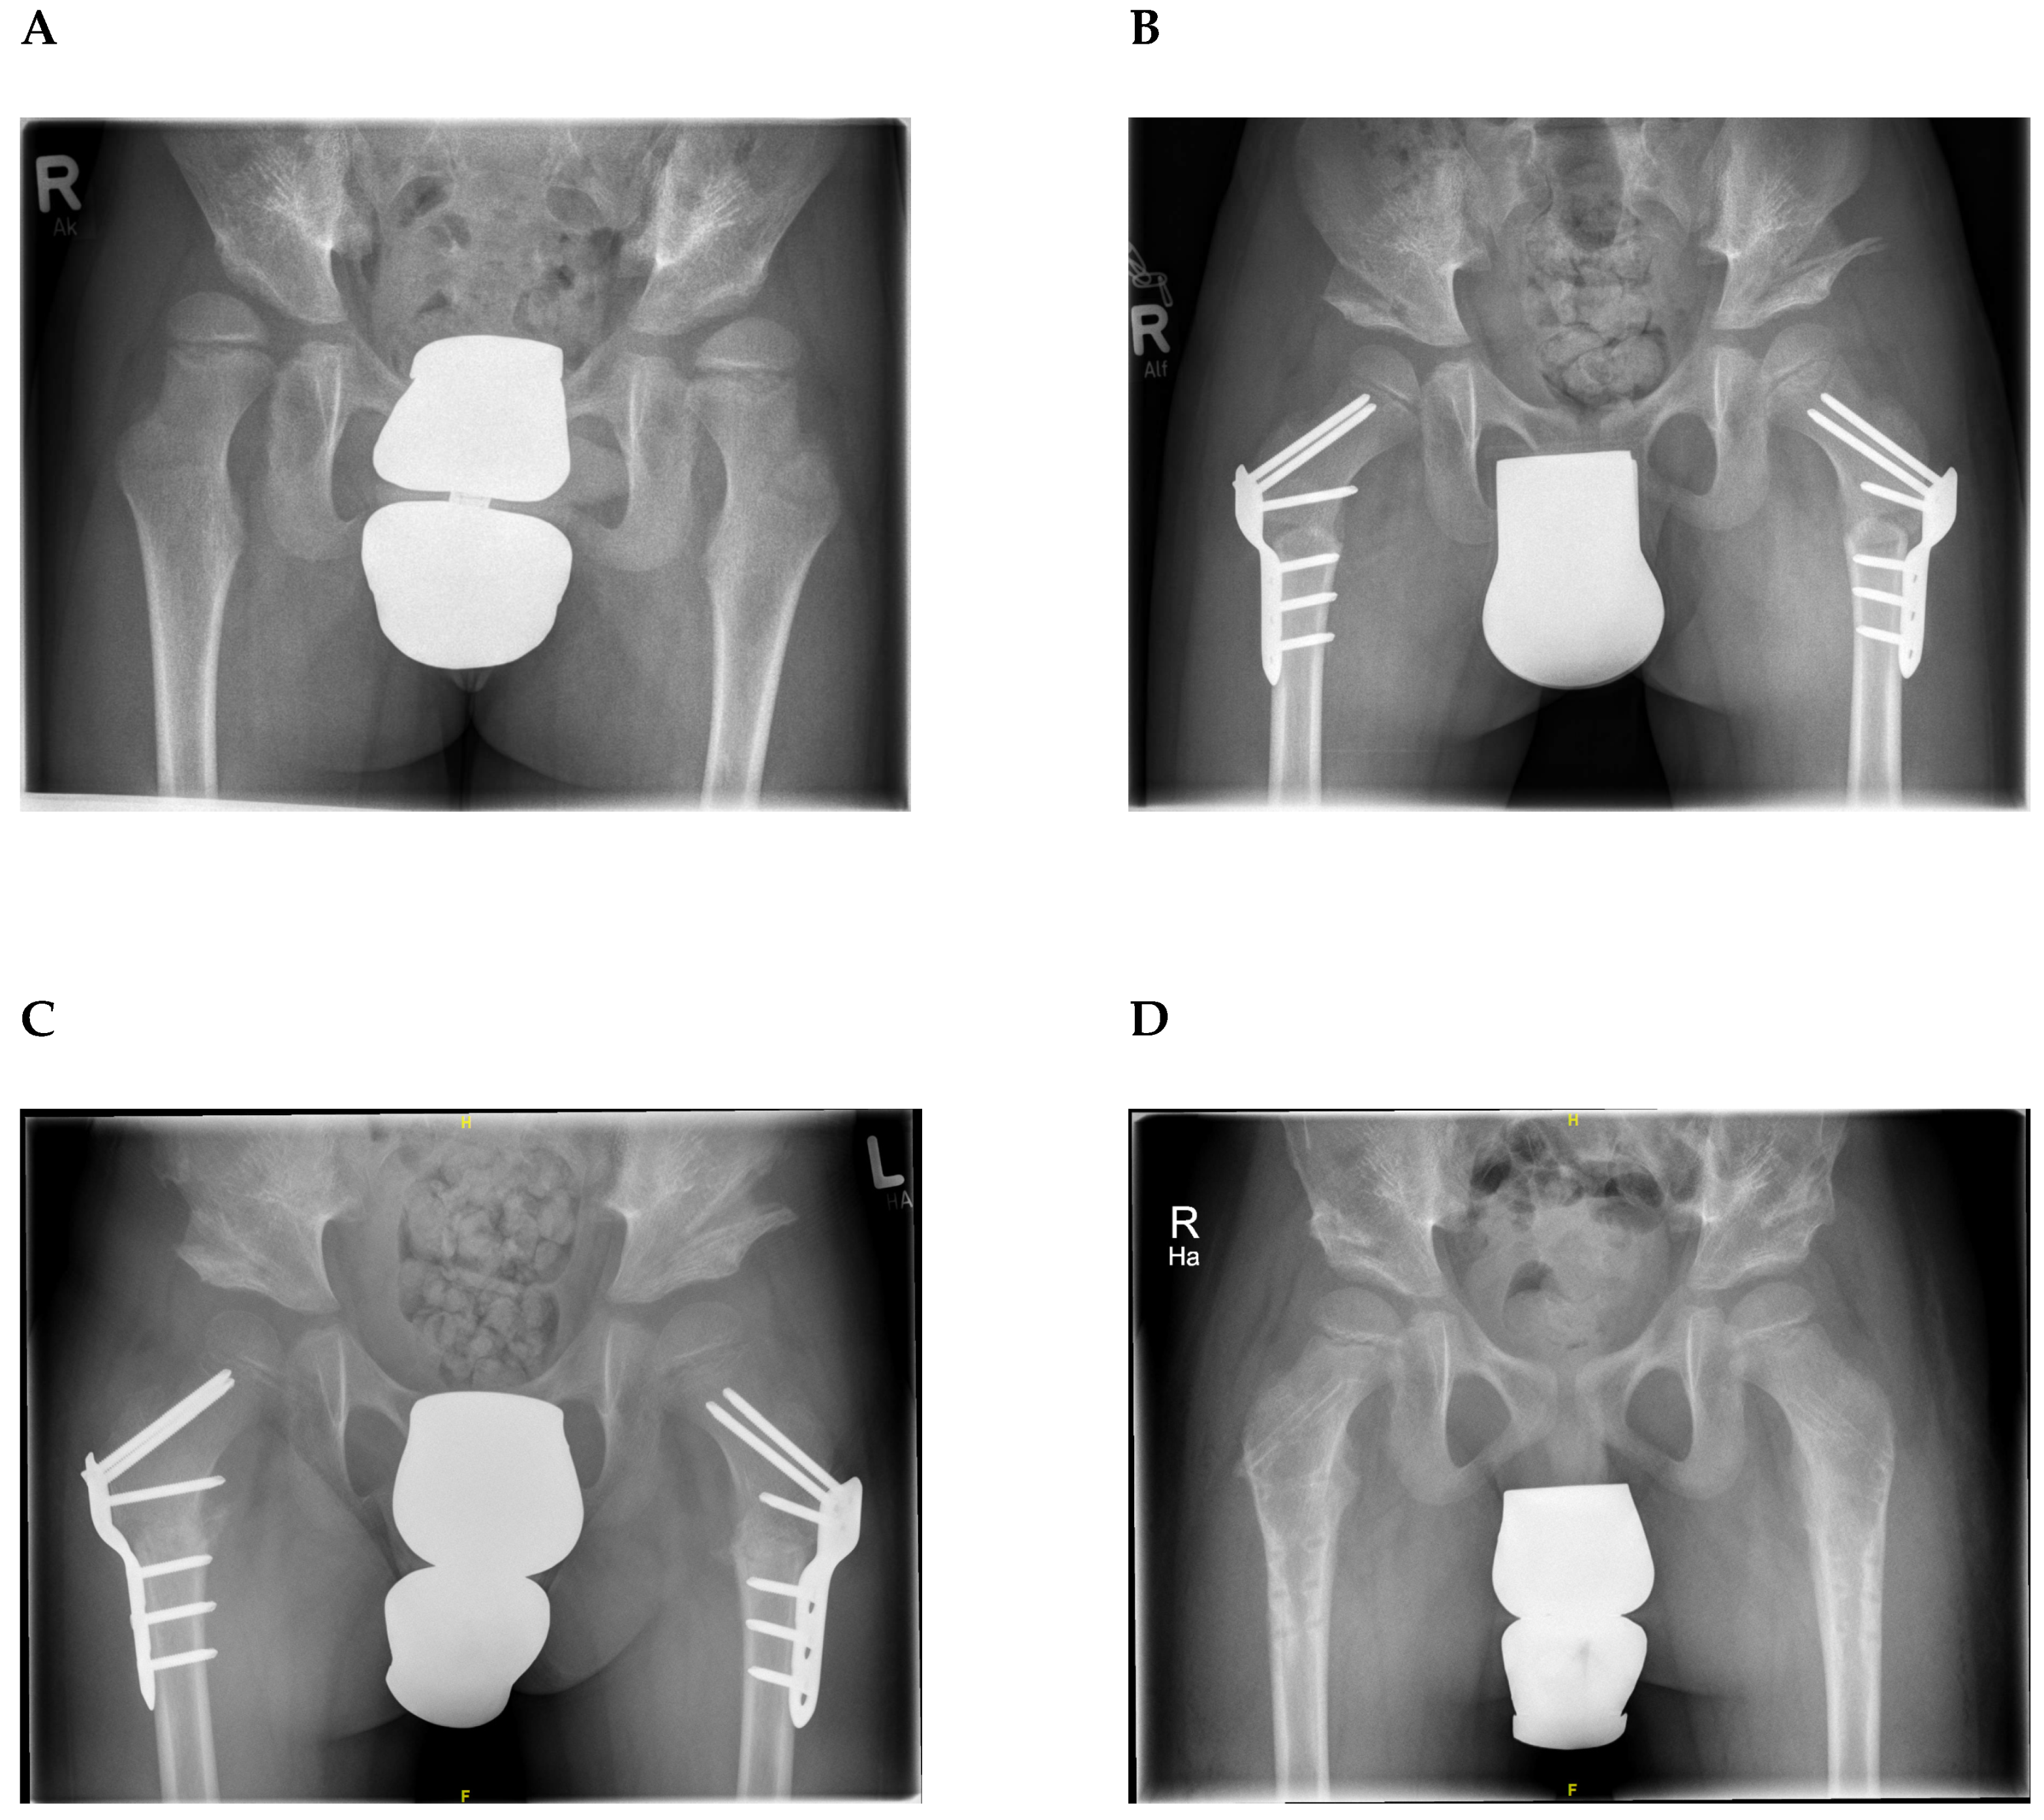

2.3. Surgical Procedure and Perioperative Care

2.4. Radiological Assessment